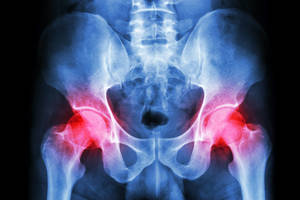

„Daugelis įsivaizduoja, kad sąnario keitimas gresia tik perkopus 60 ar 70 metų ribą, tačiau yra tekę tokią operaciją atlikti ir 22 metų vaikinui. Jam buvo diagnozuota aseptinė nekrozė – kraujotakos sutrikimai klubo sąnaryje. Kadangi liga buvo stipriai pažengusi, neliko kitos išeities kaip sudėtinga operacija. Šiuo metu tokios pat operacijos laukia 27 metų pacientas, kuris kenčia nuo sąnario susidėvėjimo – artrozės“, – sako ortopedas-traumatologas.

Gydytojo teigimu, įvairios sąnario patologijos išryškėja vis jaunesniame amžiuje. Ir dėl nuolat aktyvėjančio gyvenimo būdo, rizikingo noro pasiekti greitų sporto rezultatų, sąnarių problemos ateityje palies vis daugiau jaunų žmonių. Svarbu jas spręsti kuo anksčiau, kad pažeidimas ar liga neturėtų rimtos įtakos gyvenimo kokybei, nes kartais diagnozė gali būti ypač rimta.